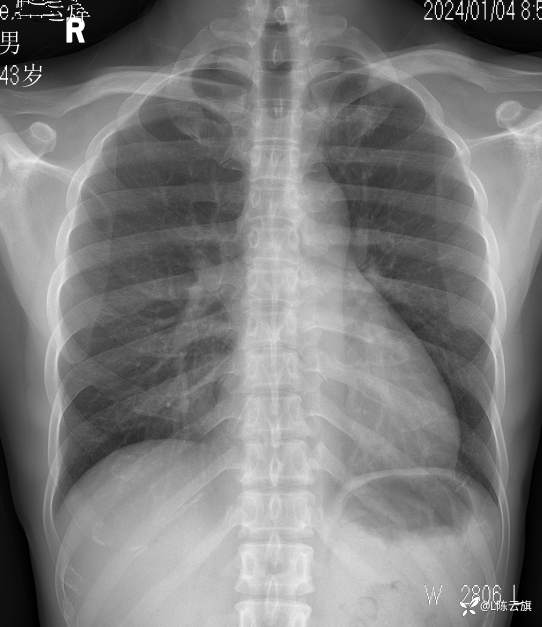

【2403胸部影像病例】 胸部平片你看到的这是什么基本病变?

1、患者男,44岁,精神长期住院患者。近一年反复发热、咳嗽、咳痰,无其他症状。每次进行胸片检查发现肺部炎时,经治疗后病灶吸收,不久又复发。

2、是否可以试述一下病变在哪里?是什么基本病变吗?

胸片1: